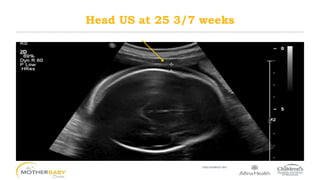

Head US at 25 3/7 weeks

Head US at25 3/7 weeks